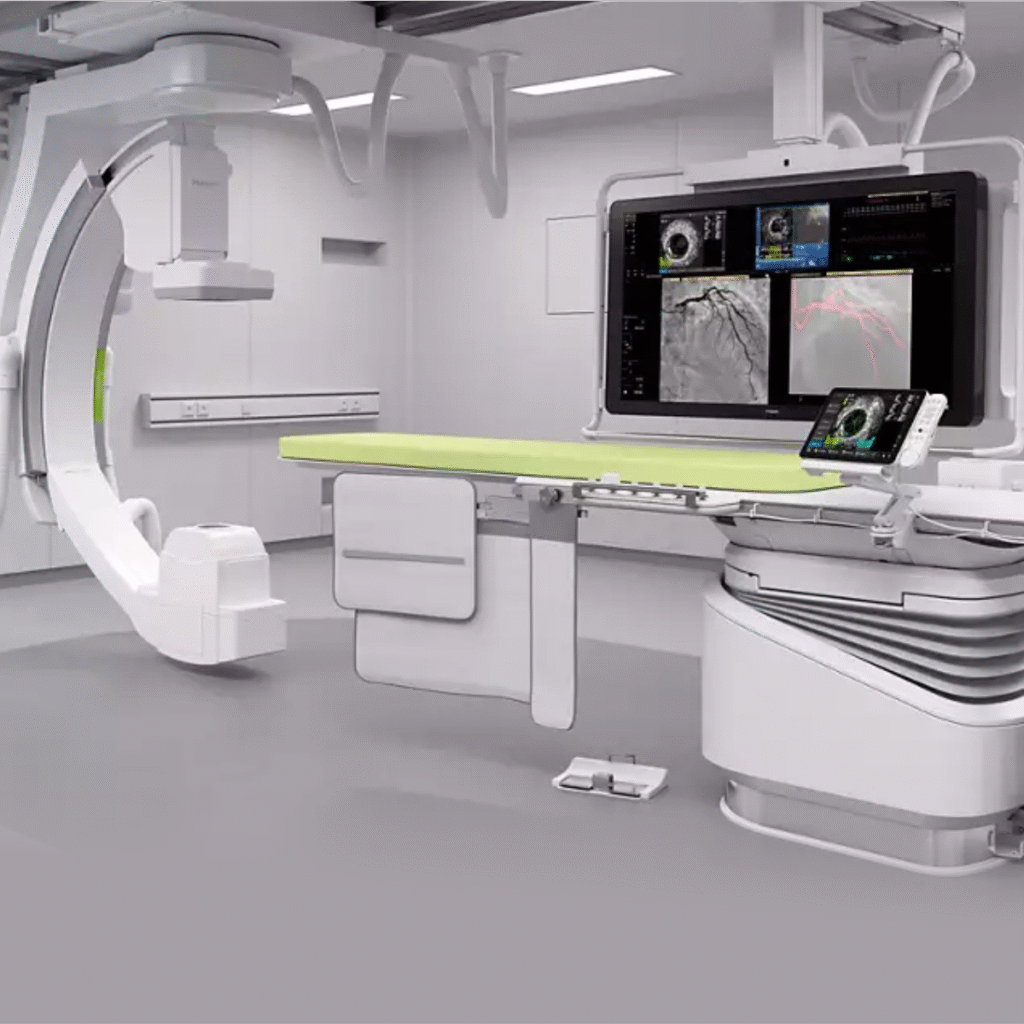

State of the Art Cath-Lab

Advanced technology for precise cardiac diagnosis and treatment.

Advanced Machines

Cutting-edge technology like the Philips Azurion Cathlab, 3D mammography, and AI-powered diagnostics.

State of the Art Philips Azurion 3.3 Cath-Lab